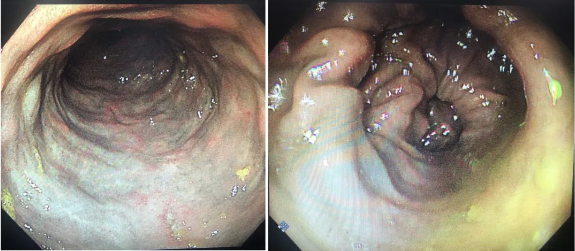

患者的肠道

前来会诊的消化内科(一)张冰凌主任医师结合一系列检查,诊断老刘为“特发性肠系膜静脉硬化性结肠炎”并已经诱发缺血性肠梗阻,老刘被收治入院接受进一步治疗。

“患者会腹痛、腹胀、恶心、呕吐等,还可能表现为腹泻、便秘、大便带血等,严重时可导致肠出血、肠穿孔、甚至肠坏死!”张冰凌主任医师介绍,老刘患上的“特发性肠系膜静脉硬化性结肠炎”(IMP)是一种罕见的慢性缺血性肠病,以结肠壁增厚、非血栓性、非炎症性肠系膜静脉狭窄或闭塞为主要特征。